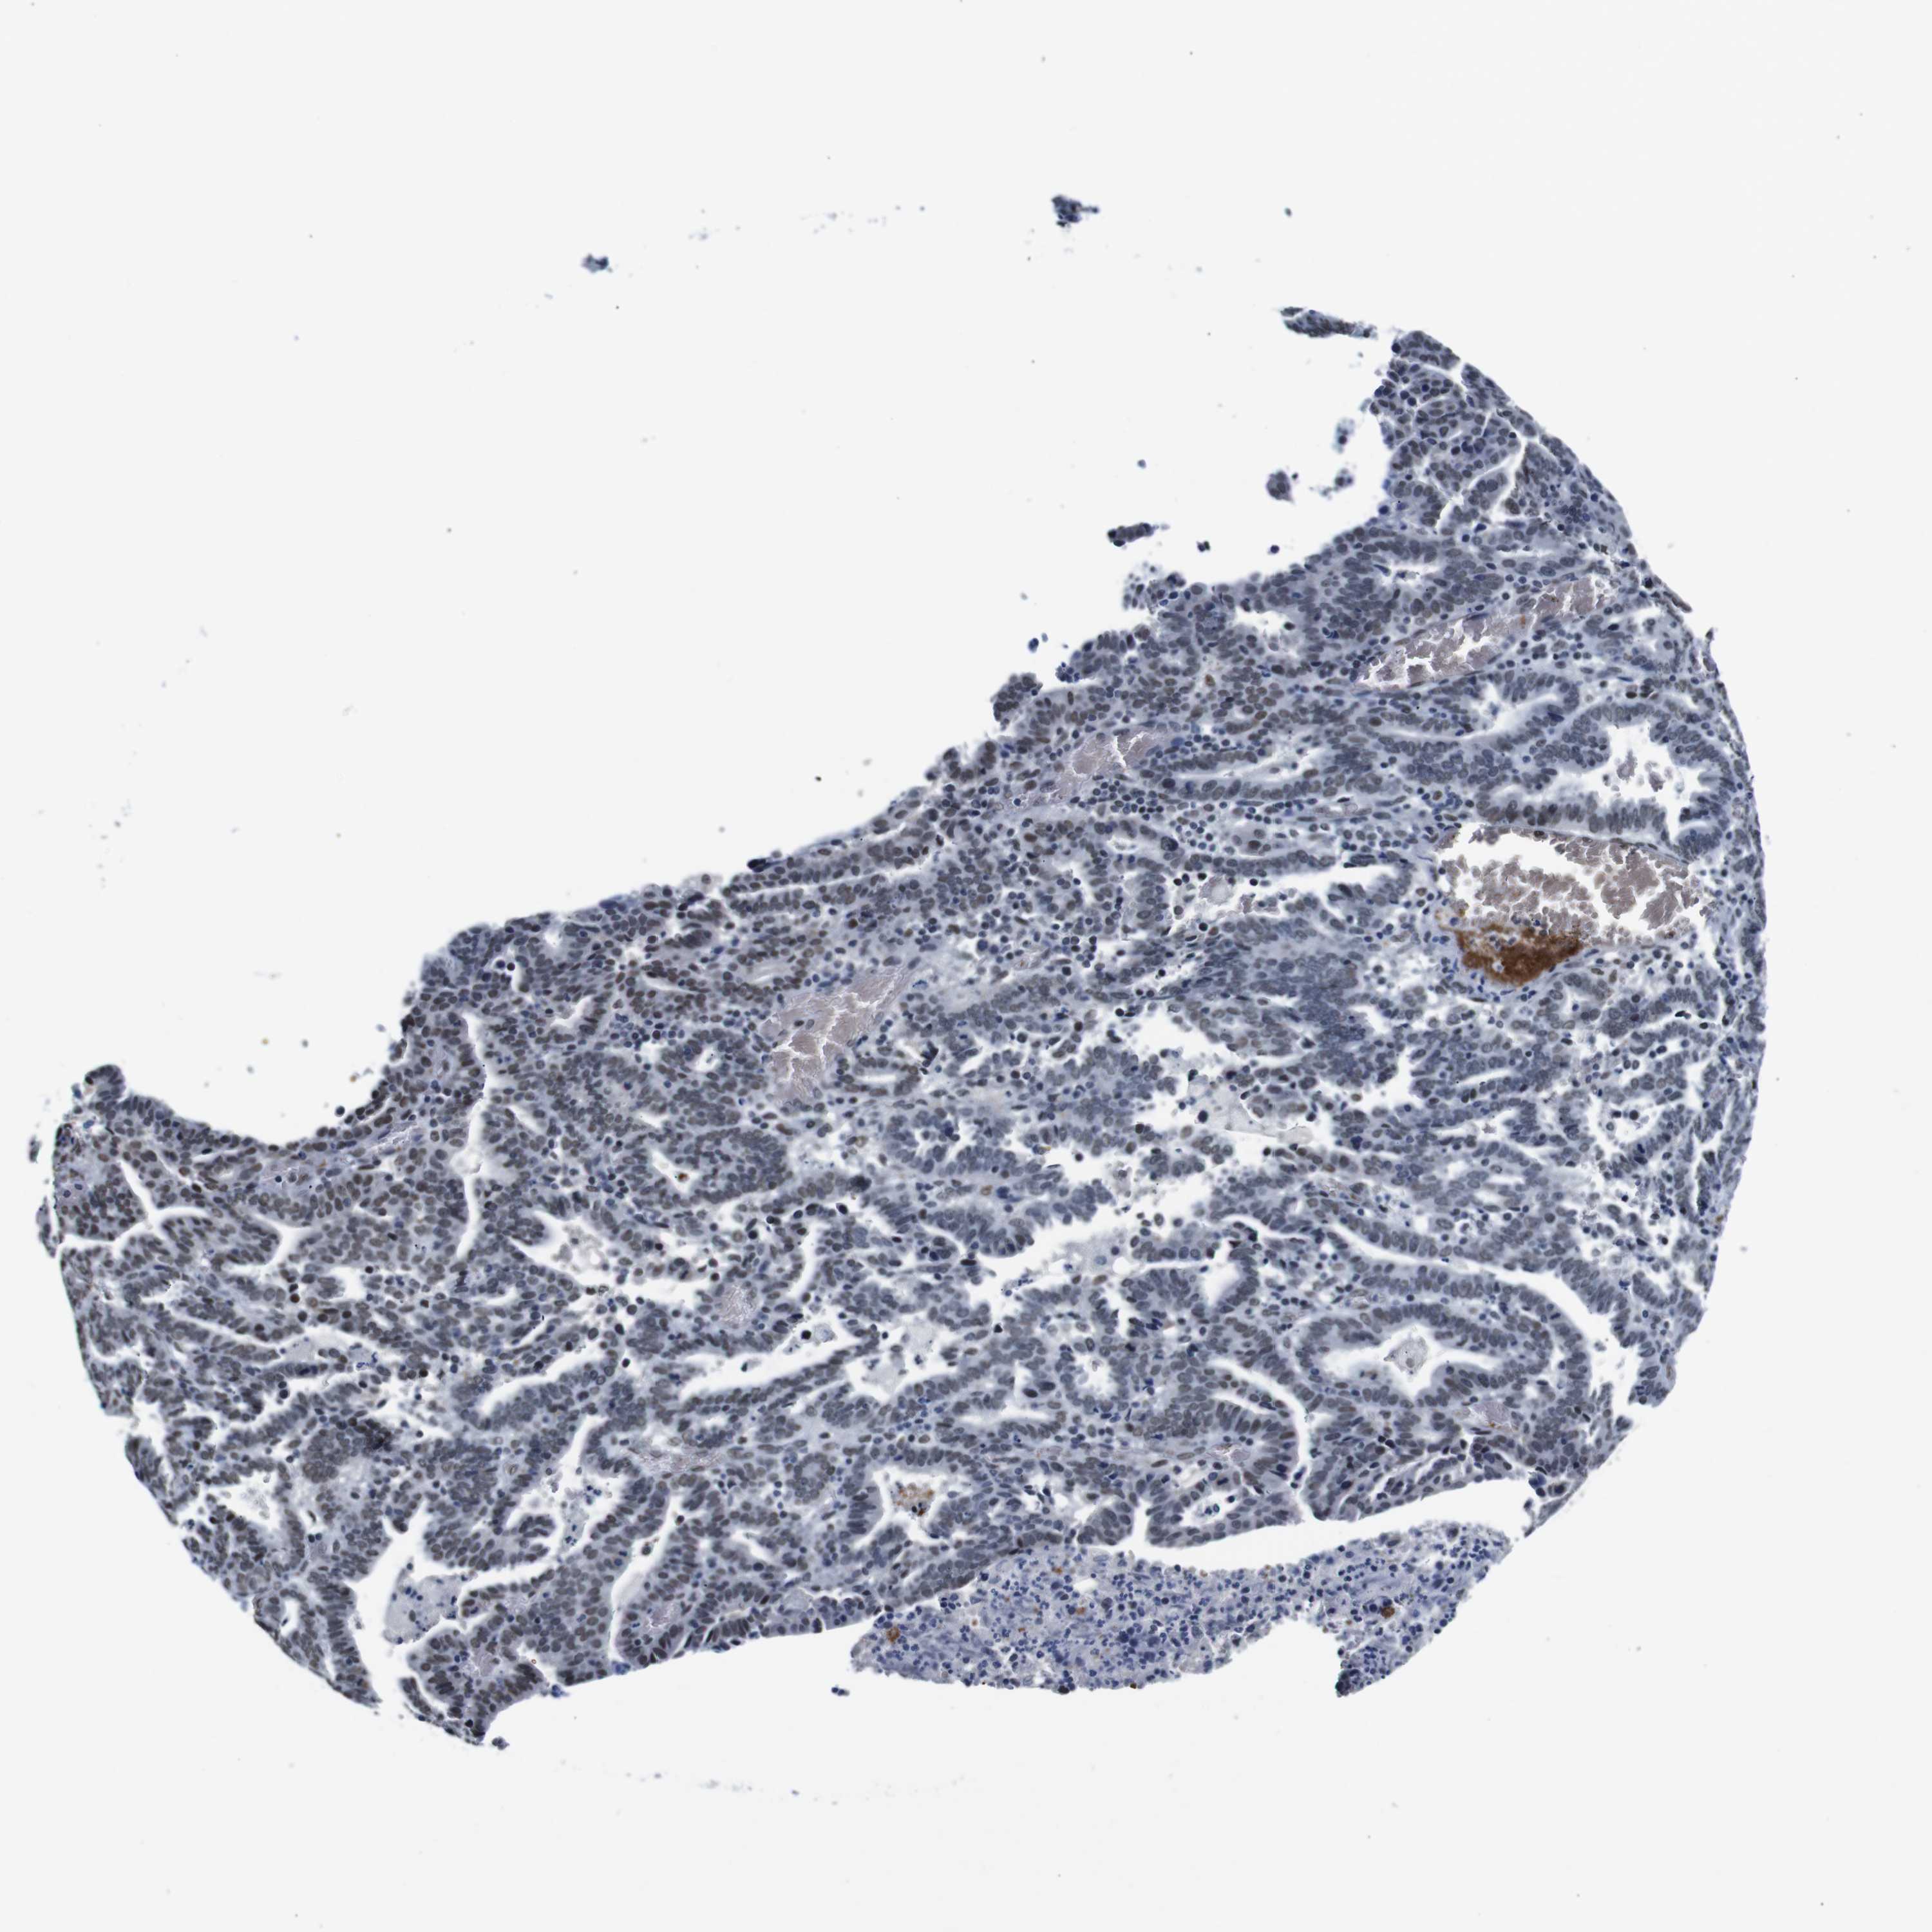

ENDOMETRIAL CANCER - Protein expressioni

A mouse-over function shows sample information and annotation data. Click on an image to view it in a full screen mode. Samples can be filtered based on level of antibody staining by selecting one or several of the following categories: high, medium, low and not detected. The assay and annotation is described here.

Note that samples used for immunohistochemistry by the Human Protein Atlas do not correspond to samples in the TCGA dataset.

Antibody stainingi

Antibody staining in the annotated cell types in the current human tissue is reported as not detected, low, medium, or high, based on conventional immunohistochemistry profiling in selected tissues. This score is based on the combination of the staining intensity and fraction of stained cells.

Each image is clickable and will lead to virtual microscopy that enables deeper exploration of all samples and also displays staining intensity scores, fraction scores and subcellular localization as well as patient and tissue information for each sample.

Antibody HPA012545

Staining

High

Medium

Low

Not detected

Intensity

Strong

Moderate

Weak

Negative

Quantity

>75%

75%-25%

<25%

None

Location

Nuclear

Cytoplasmic/membranous

Cytoplasmic/membranous,nuclear

Adenocarcinoma, NOS

Neoplasm, malignant, NOS